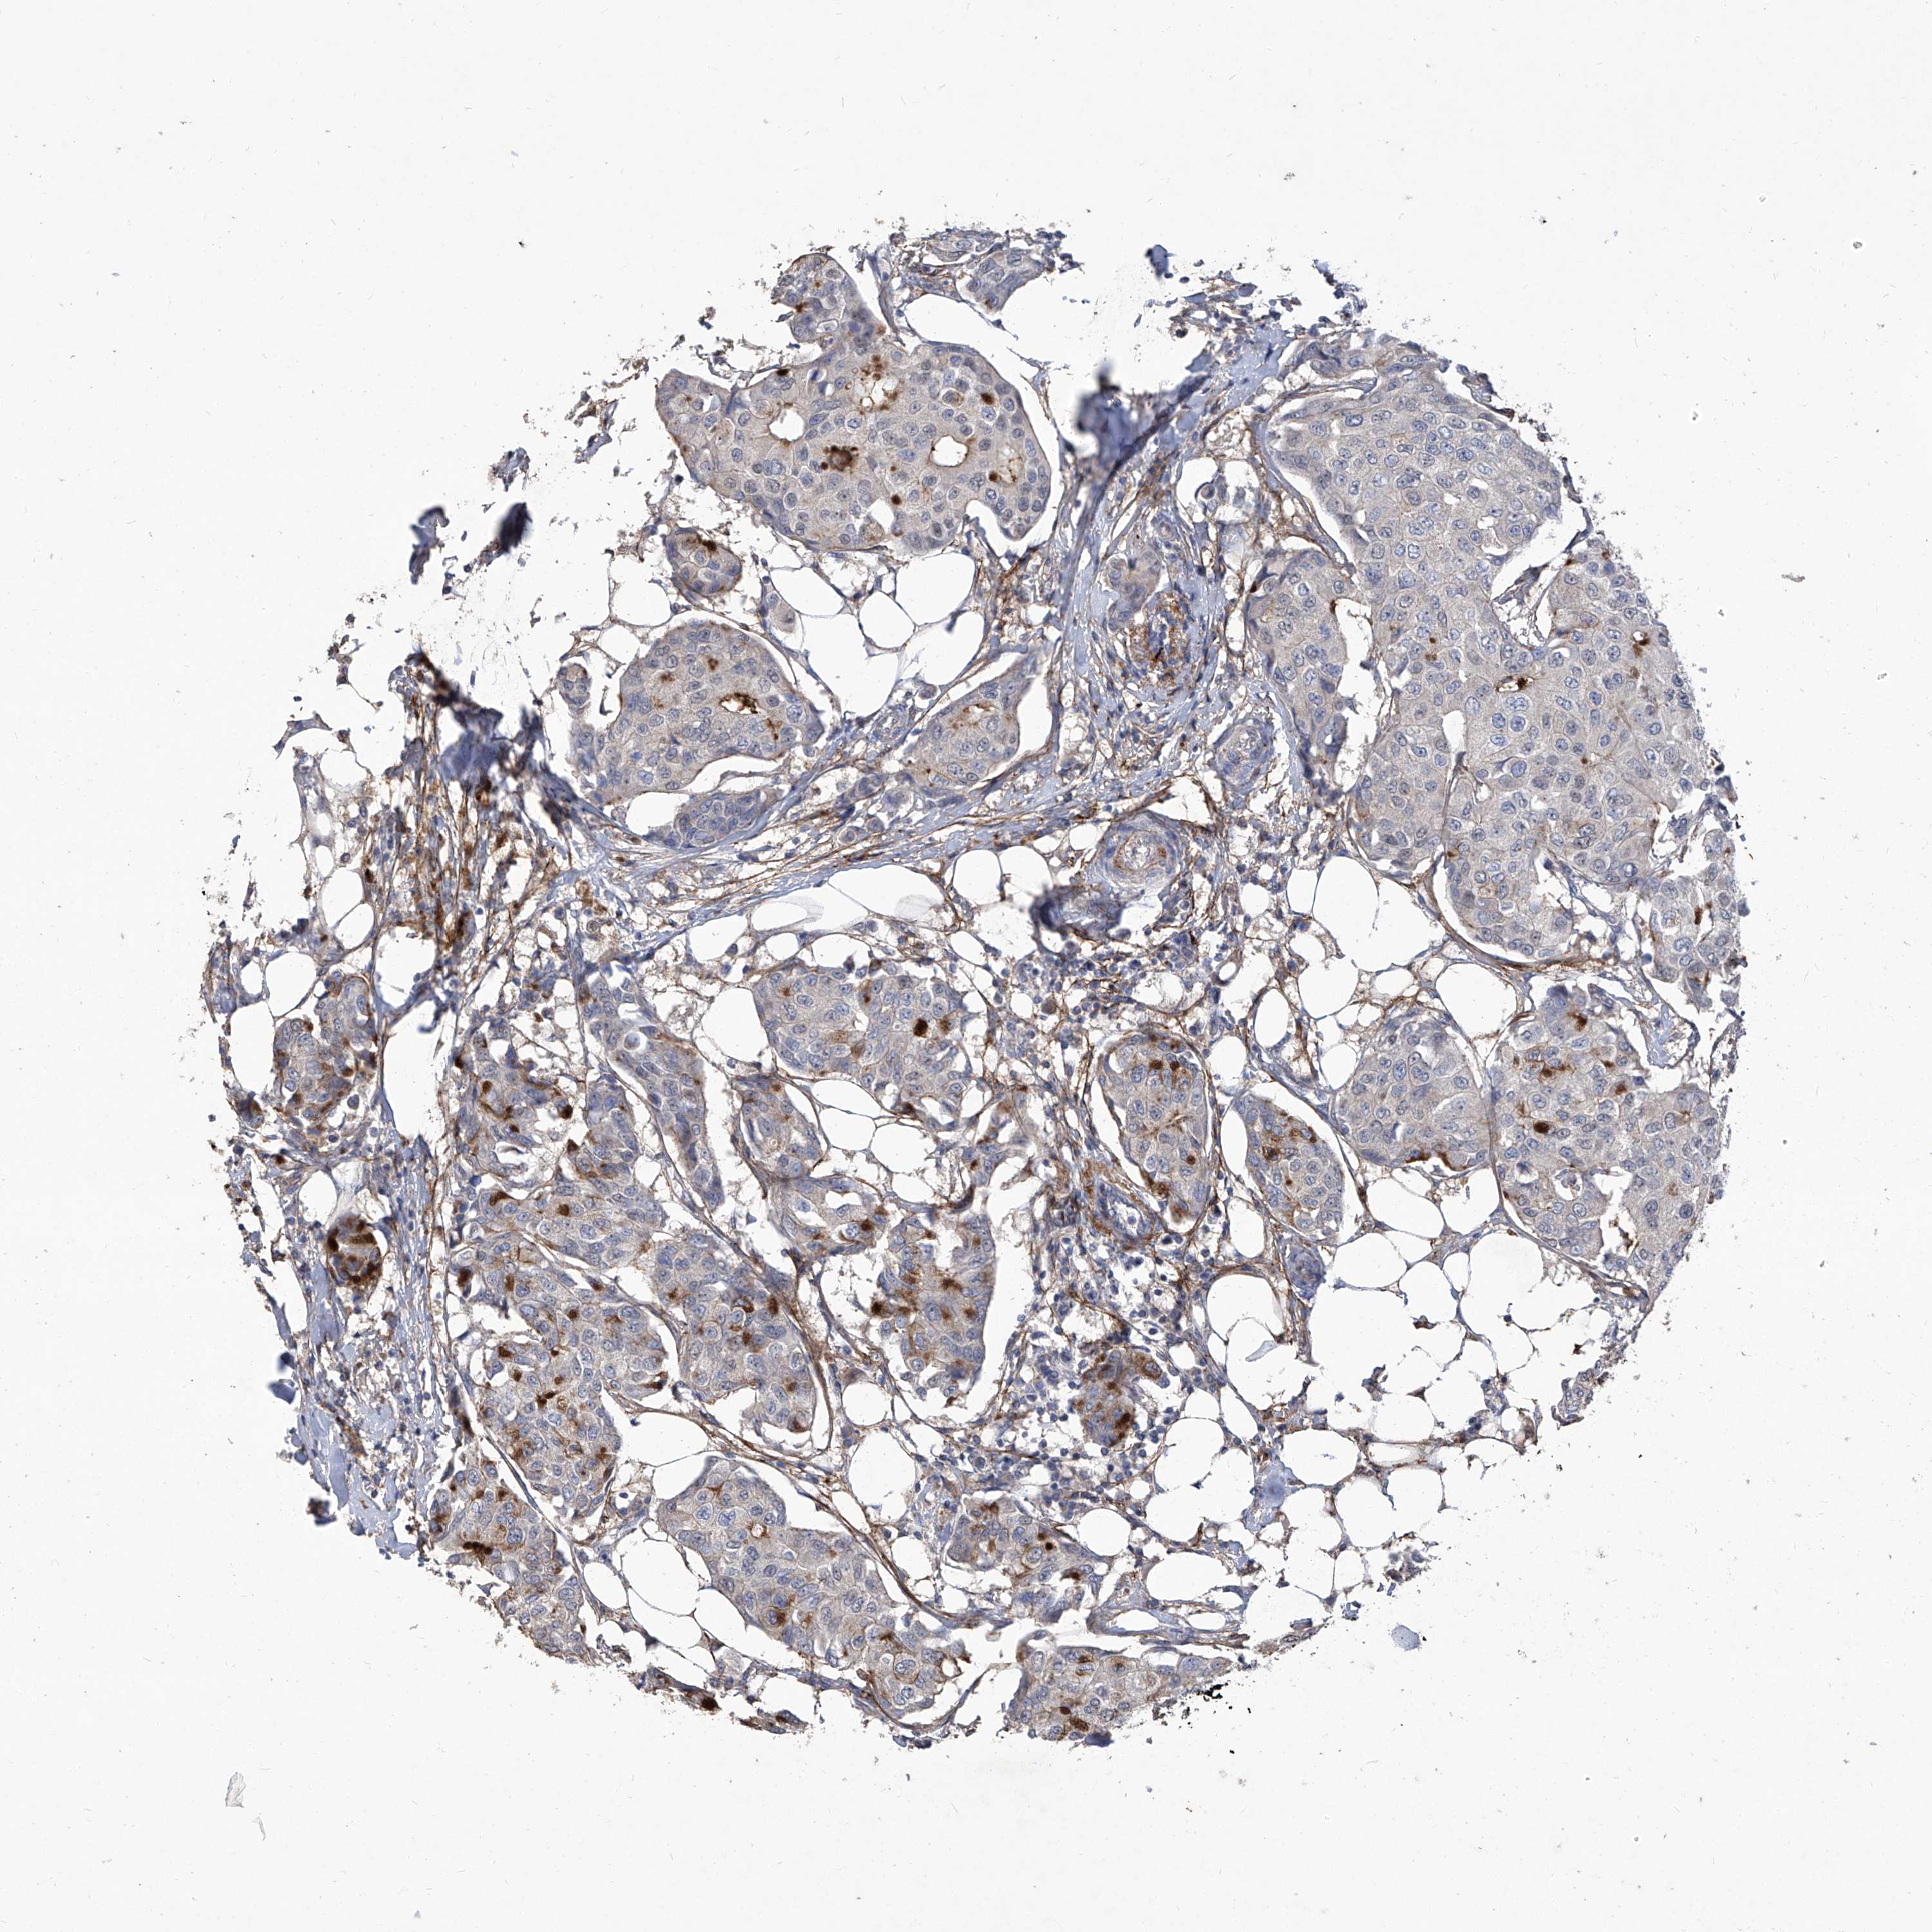

CANCER BREAST CANCER Show tissue menu

BRCA TCGA BRCA VALIDATION PROTEIN EXPRESSION

Breast cancer

Human cancer